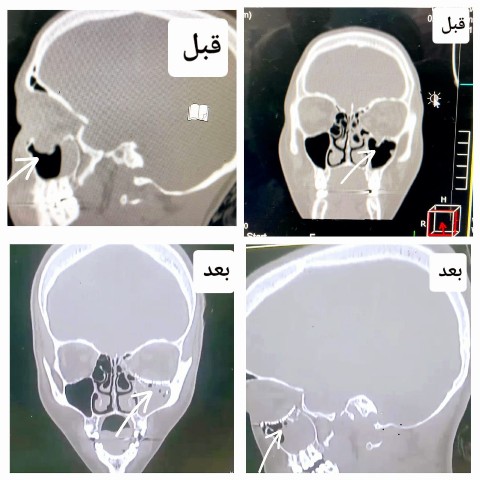

نجاح أول عملية لإعادة بناء قاع العين فى مستشفى أجا بالدقهلية

أعلن الدكتور تامر مدكور وكيل وزارة الصحة بالدقهلية أن فريق طبي في مستشفى أجا قد نجح في إجراء أول عملية لإعادة بناء قاع العين حيث تعتبر من العمليات الكبرى والمعقدة في جراحة الوجه والفكين.

وأضاف مدكور أن مستشفى أجا كانت قد استقبلت مريضة تعاني من كسر بقاع العين أدي إلى حدوث خلل بعضلات العين وازدواجية بالرؤية نتيجة الكسر وتم عمل فحص للعين والتأكد من سلامتها وومن ثم تجهيز المريضة للعمليات .

ومن جهته أكد الدكتور أحمد البيلى وكيل المديرية للطب العلاجى أن العملية كأول عملية بعد افتتاح قسم جراحة الوجه والفكين في المستشفى مؤخراً والذي يقوم بتشخيص وعلاج وجراحة كسور الوجه والفكين والجمجمة والأورام الحميدة والانتانات المرضية في الوجه والفكين وعلاج أمراض التشوهات الخلقية في الوجه والفكين.